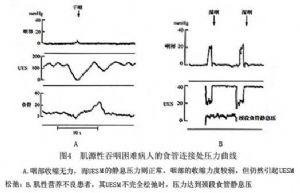

神經性口咽性運動功能障礙表現爲食管上括約肌靜息壓異常、不協調和鬆弛障礙(圖3)。肌源性口咽性下嚥困難患者咽部的收縮力較弱,持續時間也較長。其收縮力不足以將食團推經食管上括約肌,使得食管上括約肌成爲食物推進的障礙(圖4)。